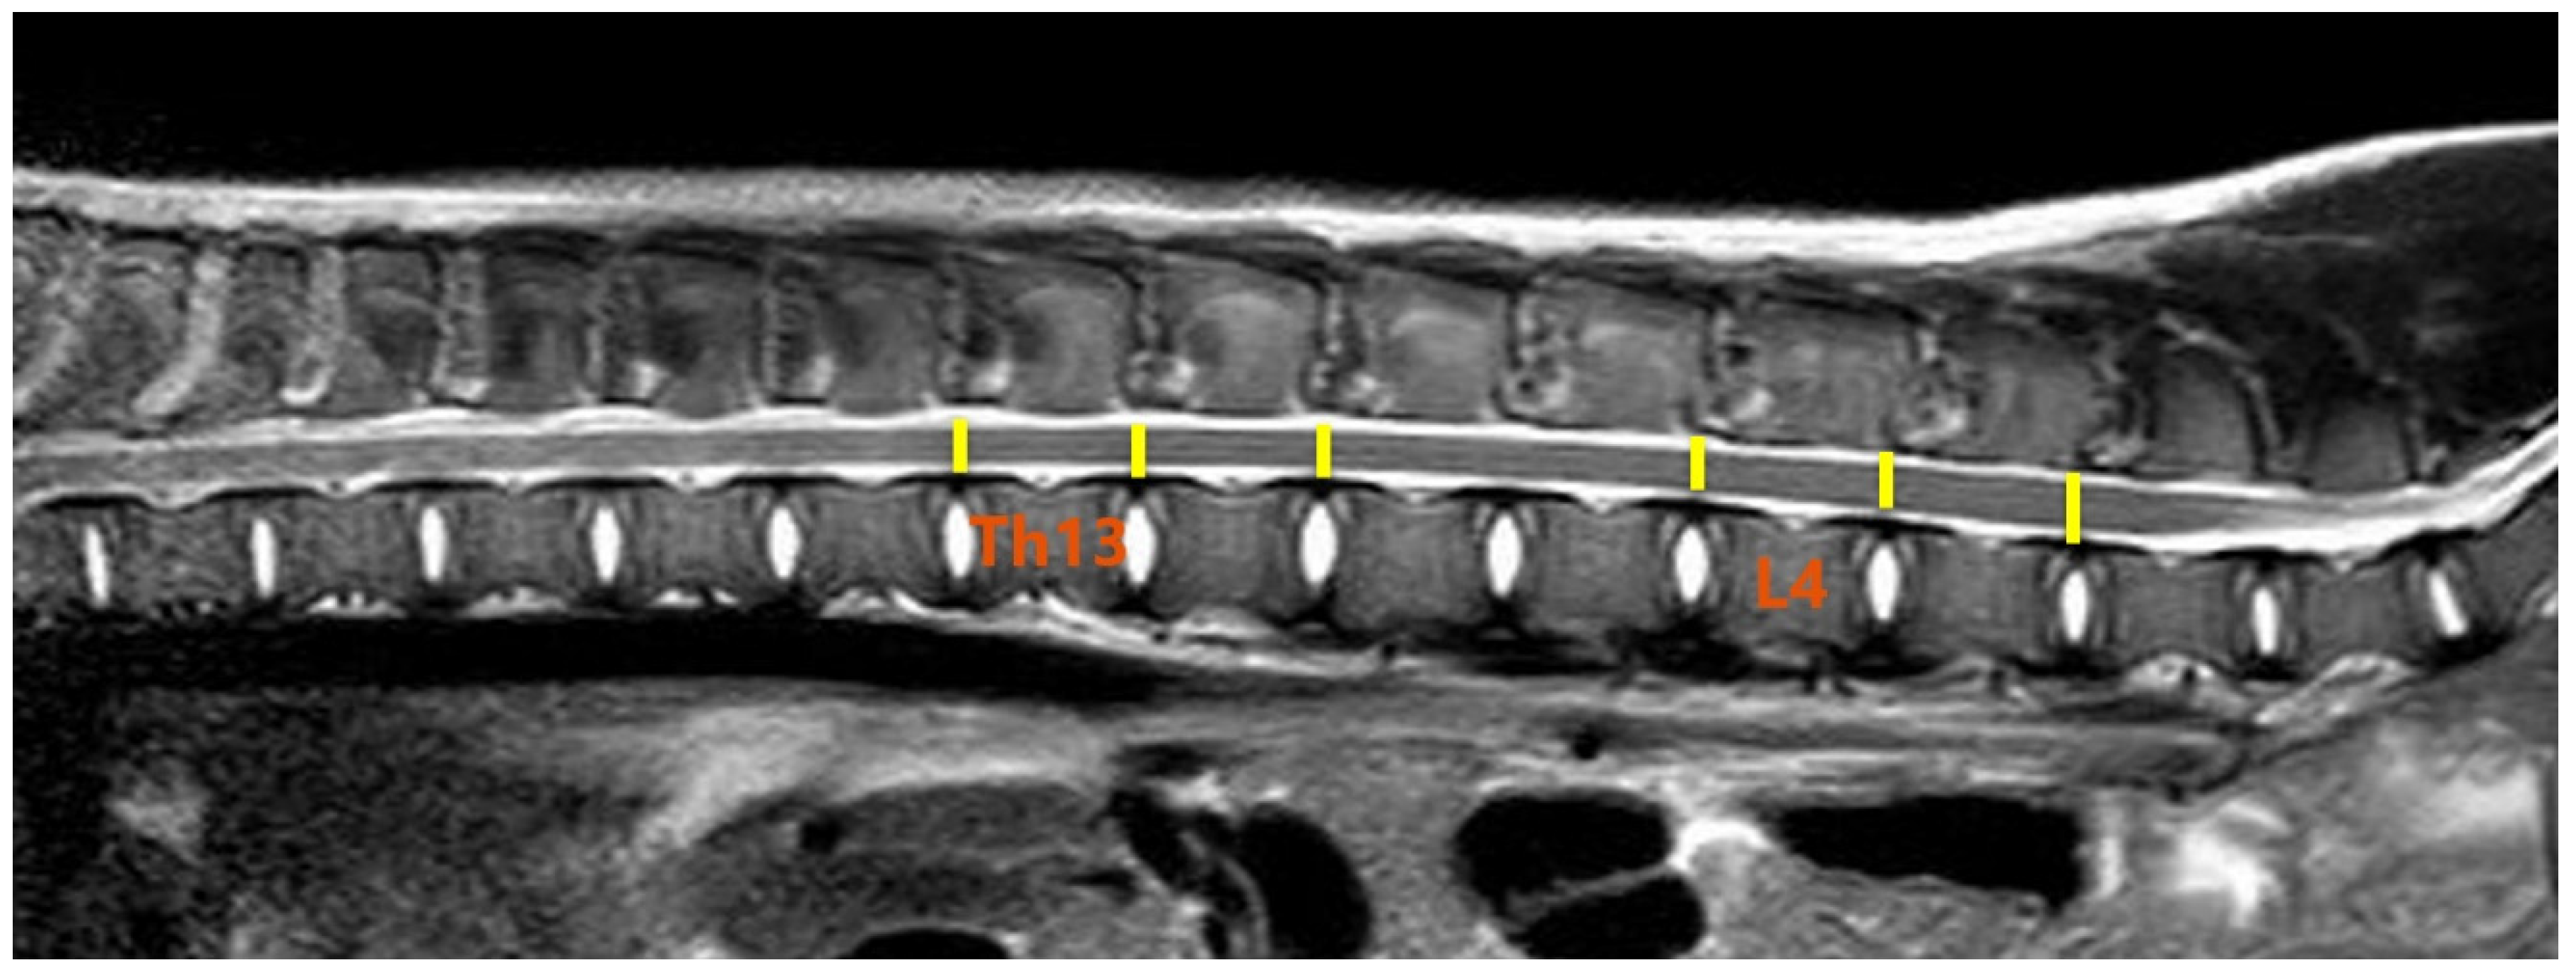

2.3. MR Imaging and DTI Protocol

2.4. Image and DTI Analysis